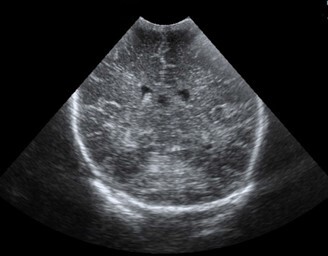

Neonatology Choroid Plexus 1 Image